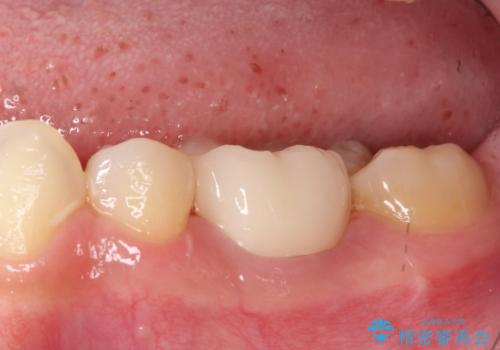

まず、右上6・右下6の根管治療を再度行い、根の状態をしっかり整えた上で、セラミッククラウンを装着しました。さらに、欠損していた右上7・右下7にはインプラントを埋入し、セラミッククラウンを装着。治療後は、「奥歯でしっかり噛めるようになり、不安なく食事ができるようになった」と患者様にも大変ご満足いただきました。